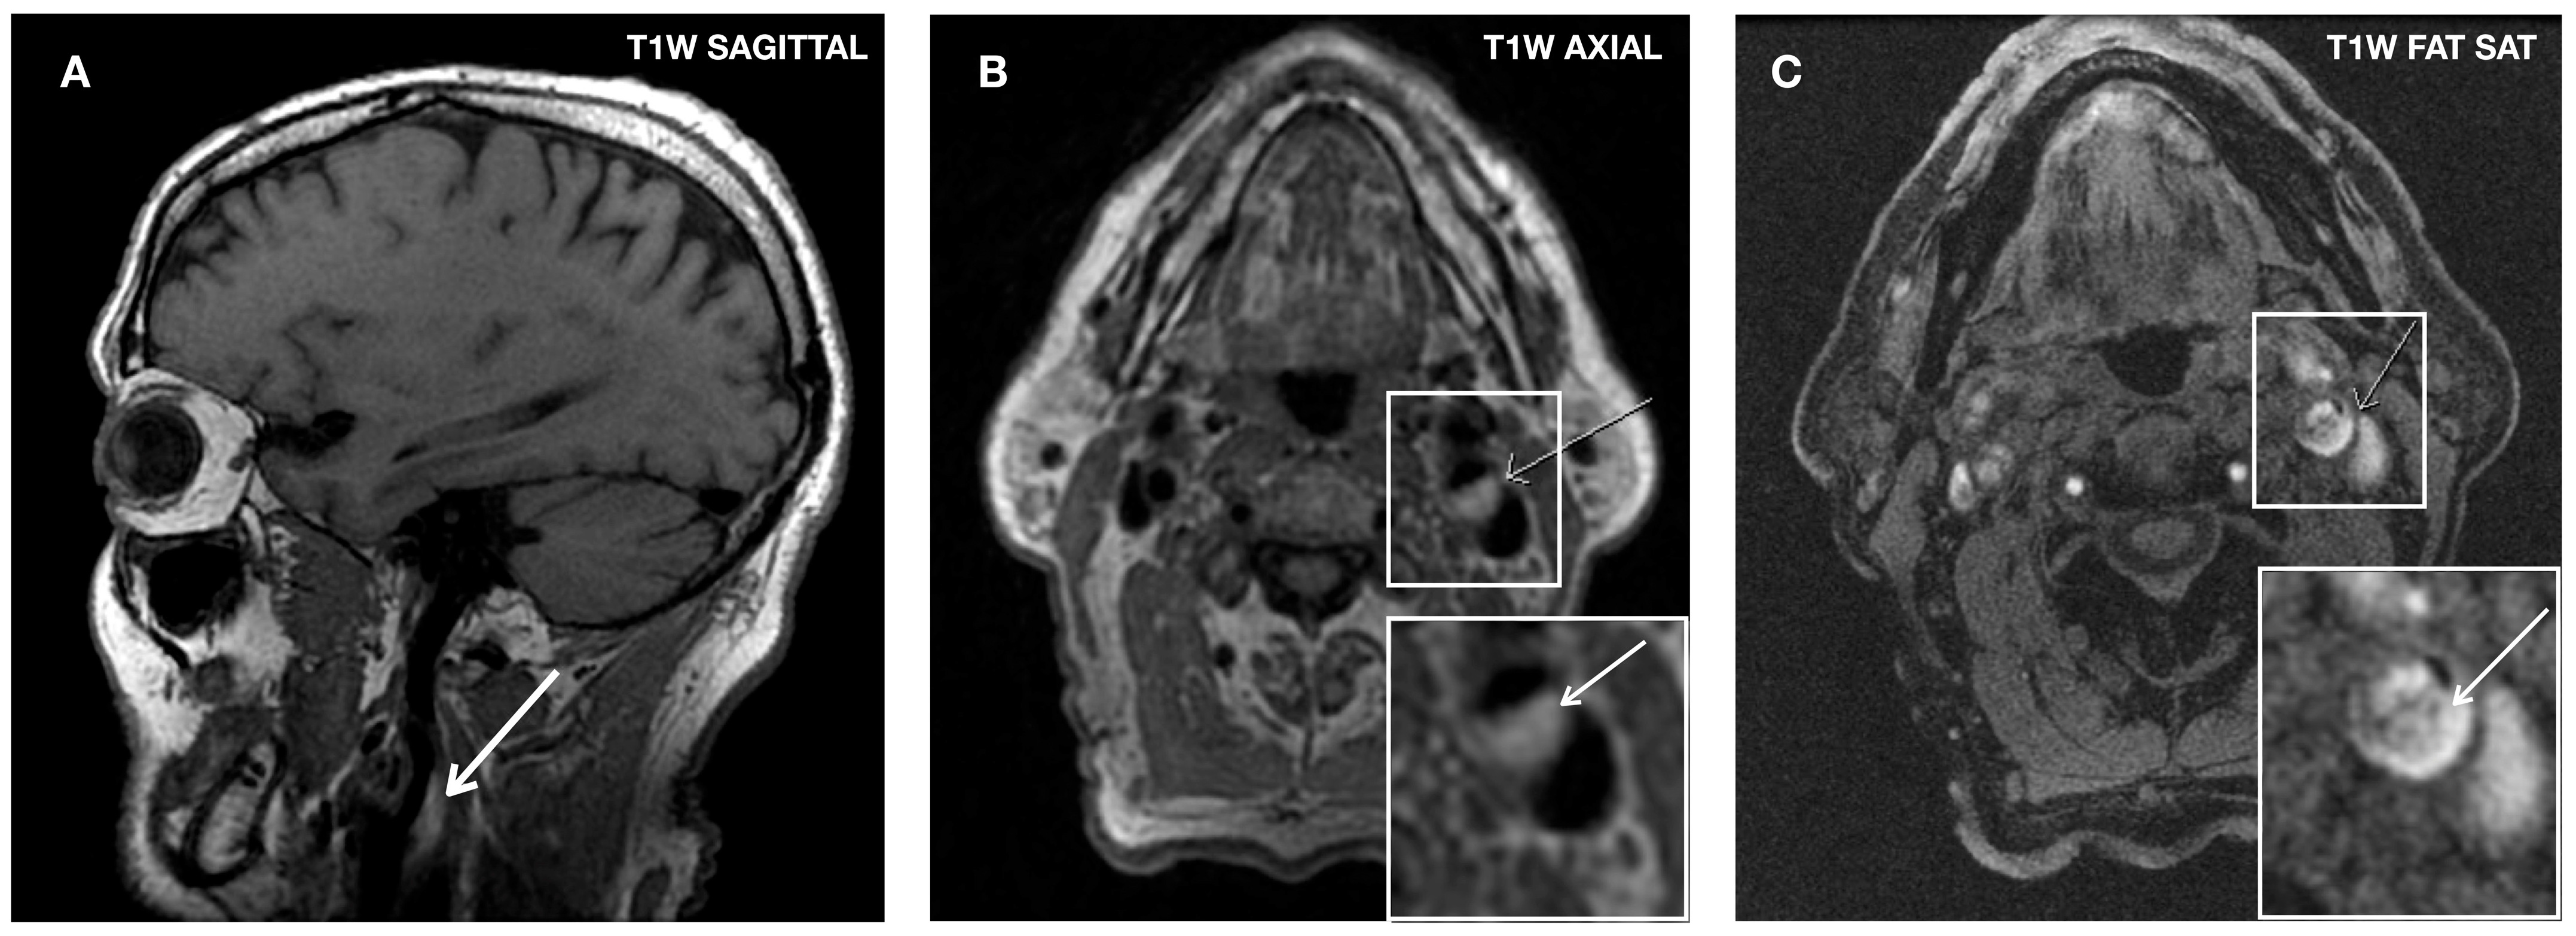

3.6. Carotid Magnetic Resonance Imaging (MRI)

Histological correlation studies have demonstrated the high sensitivity and specificity of in vivo high-resolution MRI in identifying vulnerable plaque characteristics [144]. The best potential of MRI lies in estimating the thickness of the fibrous cap and detecting the presence of IPH, being particularly adept at distinguishing between LRNC and IPH [32]. MRI has proven clinically valuable in detecting IPH with a sensitivity ranging from 82% to 97% and a specificity of 74% to 100% [145,146] (Figure 6).

Figure 6.

MRI images of an IPH. T1-weighted (T1W) sagittal (A) and axial views (B) show hyperintense signal within the carotid plaque (white arrows). On the T1W with fat saturation image (C) the plaque also presents areas of high intensity, indicating the presence of IPH.